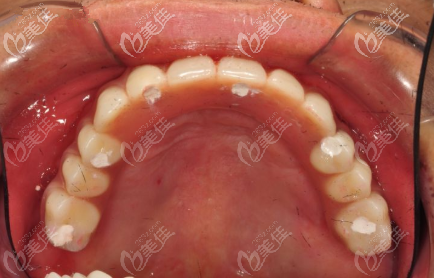

術(shù)前診斷:

這位患者上頜無牙頜,上半口全牙缺失,拍片診斷后,設(shè)計了All-on-6半口種植,也就是上頜采用6個種植體支撐即刻負(fù)重的半口無牙頜修復(fù)體。也就是說只需要6顆種植體就可以修復(fù)半口缺牙。

即刻修復(fù)種植后,手術(shù)當(dāng)天戴牙。種植體品牌選的是諾貝爾Active,也是諾貝爾nobel種植體三大型號里面比較常用的。這個案例中諾貝爾Active種植體的價格為2W一顆,收費標(biāo)準(zhǔn)在西安來說適中。